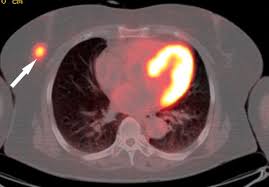

The test has only a limited ability to detect small tumors. Pet scan for breast cancer a positron emission tomography (pet) scan is an imaging test that uses a radioactive substance (called a tracer) to look for potential spread of breast cancer. In some instances, cancers may not show on the scan. Combining a pet scan with an mri or ct scan can help make the images easier to interpret. Pet scans can be used to determine how much cancer is in a person's body and how far the cancer has spread, which is called staging. This tracer can help identify areas of cancer that an mri or ct scan may miss. With cancer cells, they appear as bright spots due to its higher metabolic rate compared to normal cells. However, the pet scan uncovers every unusual activity in the body and is more sensitive than any other existing imaging test. Pet/ct scan can accurately localize lymph node metastasis and help to monitor the response to chemotherapy. Breast positron emission tomography (pet) scan is an imaging test that uses a tracer (radioactive substance) to look for symptoms of breast cancer. Pet scans can also help to assess whether metastatic breast cancer is responding to the treatment. Pet scans are not used to screen women for breast cancer. Pet/ct scans using axumin tracer, approved by fda last year and newly approved by medicare in some areas, are starting to be done at different locations.

The Clinical Utility Of Fdg Pet Ct In Follow Up And Restaging Of Breast Cancer Patients Sciencedirect from ars.els-cdn.com Pet scan is a type of test that may be used in cancer treatment. A ct scan produces multiple images, providing a detailed picture of the internal anatomy, including the location of cancerous growths. If you have a large breast cancer, your doctor may order a ct scan to assess whether or not the cancer has moved into the chest wall. This substance is often called a tracer, because it helps reveal cancer in the body. It is similar to a pet scan, but it uses a different radioactive substance that settles in areas of change in the bones. For cancer, pet is especially useful as it can scan the entire body and pinpoint both a primary tumor and areas of metastasis (where the cancer has spread). In some instances, cancers may not show on the scan. When breast cancer cancer spreads.

It is common for patients to receive a diagnosis for cancer of unknown primary. Types of cancer detected and treated. Its supposed to be more sensitive/specific than naf and other older scans, and comparable i think to choline or acetate (lots of studies and info on the web) and. With that being said, not all cancers can be detected by pet. A breast pet scan is often very specific and sensitive and is approved for patients. Although it is not appropriate for all patients with breast cancer, fdg pet/ct can have an important clinical effect for appropriate patients. Normally, a pet scan is not used for breast cancer screening. With cancer cells, they appear as bright spots due to its higher metabolic rate compared to normal cells. When breast cancer cancer spreads. Each has its own strengths. For cancer, pet is especially useful as it can scan the entire body and pinpoint both a primary tumor and areas of metastasis (where the cancer has spread). This test can help show if the cancer has spread to your bones. One example is a combined pet and ct scan (known as pet/ct), available in some centers.